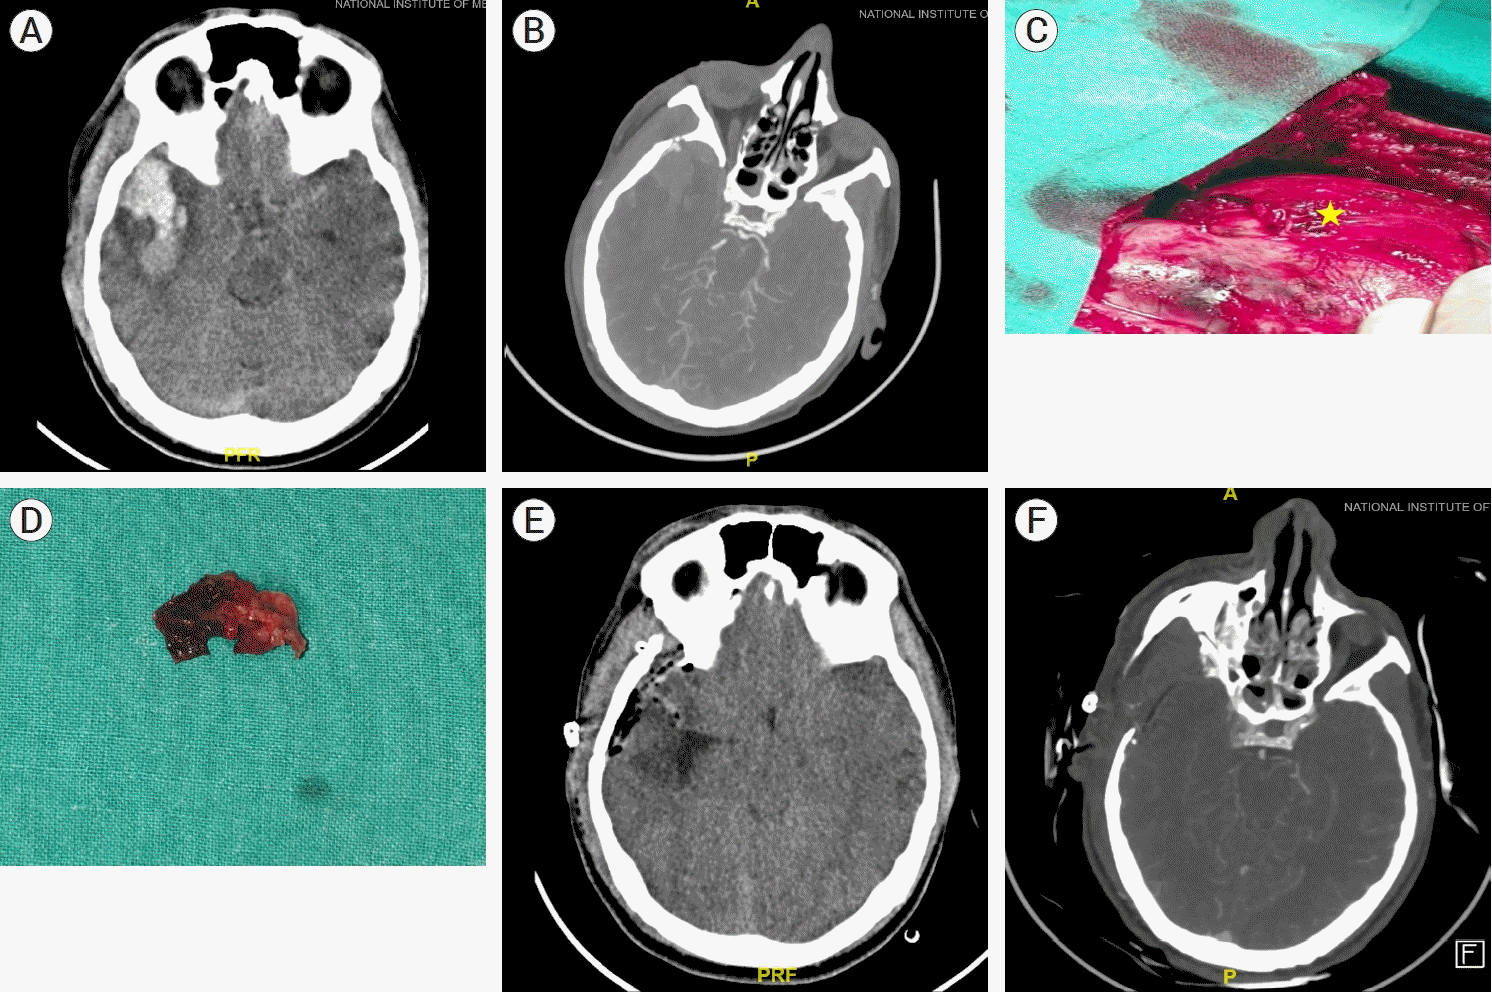

A 36-year-old male presented to emergency in an altered sensorium following a road traffic accident with a Glasgow coma scale of 10/15. A plain computed tomography (CT) of brain showed a right temporal hematoma of volume 40 cc with midline shift of 7 mm and effaced cisterns and small contusion in left temporal lobe with linear undisplaced fracture of the right temporal bone (Fig. 1A). The patient was planned for emergency evacuation of right temporal hematoma, and a CT angiography was done before shifting to the operation theatre. CT angiography showed the presence of a middle meningeal artery pseudoaneurysm with the nidus situated adjacent to the hematoma (Fig. 1B). The decision of hematoma evacuation along with aneurysm excision was made.

The patient underwent right frontotemporal craniotomy and aneurysm was located 3 cm from the sphenoid ridge as calculated from the preoperative CT scan (Fig. 1C). There was associated fracture and underlying dural tear in line with the pseudoaneurysm, providing a pathway for the hematoma to extravasate into the temporal lobe. Apart from the pseudoaneurysm, no other source of bleeding was noted intraoperatively and the pseudo aneurysm was in contact with hematoma (Fig. 1C). Upon dislodging the clot brisk bleeding from the pseudo aneurysm was also noted which was controlled with coagulation on either ends of the middle meningeal artery close to the aneurysm followed by excision of the pseudo aneurysm (Fig. 1D). The dura was then repaired with temporal fascia graft and bone flap was replaced. The patient recovered well in the post-operative period with improvement in sensorium to Glasgow Coma Scale (GCS) 15/15. Histopathological study showed the presence of aneurysmal sac with tear lined by fibrin clot. The post-operative CT angiogram showed the absence of any aneurysm along with good hematoma evacuation and opening of the basal cisterns (Fig. 1E, 1F). He was discharged on post-operative day 2 and follow-up at 6 months showed complete recovery with a Glasgow outcome scale extended score of 8.

Fig. 1.

(A) CT Plain brain shows contusion in right temporal lobe with linear undisplaced fracture of the right temporal bone. (B) CT angiogram suggestive of right middle meningeal artery pseudoaneurysm. (C) Pseudoaneurysm located close to sphenoid ridge. (D) Excision of pseudoaneurysm along with the dural cuff. (E) Post-operative CT Brain shows good hematoma evacuation with opening of the basal cisterns. (F) Post-operative CT angiogram shows the absence any aneurysm. CT, computed tomography